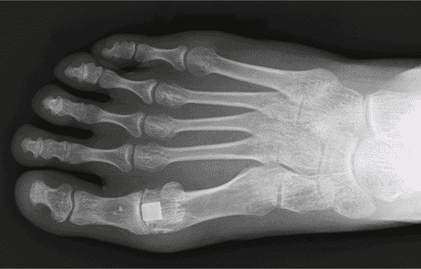

The Cartiva Synthetic Cartilage Implant was introduced as a minimally invasive alternative to traditional joint fusion surgery. Approved by the FDA in 2016, it is made from a hydrogel material designed to mimic natural cartilage and cushion the big toe joint—offering pain relief while preserving motion.

- Implant Subsidence – The implant sinks into the surrounding bone